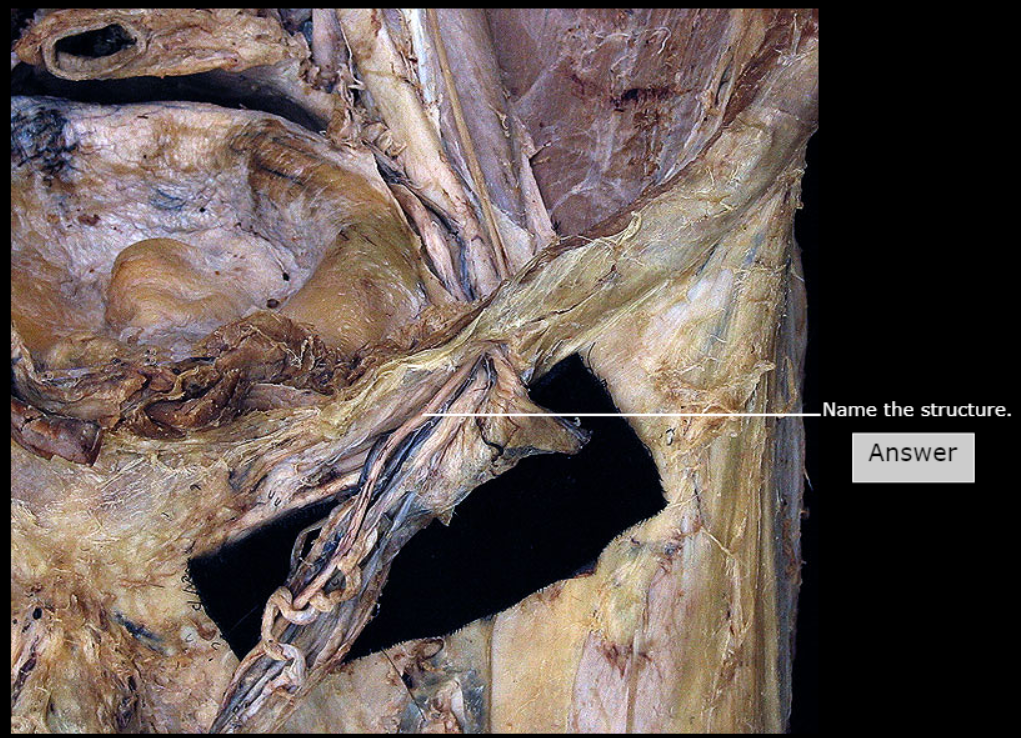

Obturator Nerve, Obturator Canal